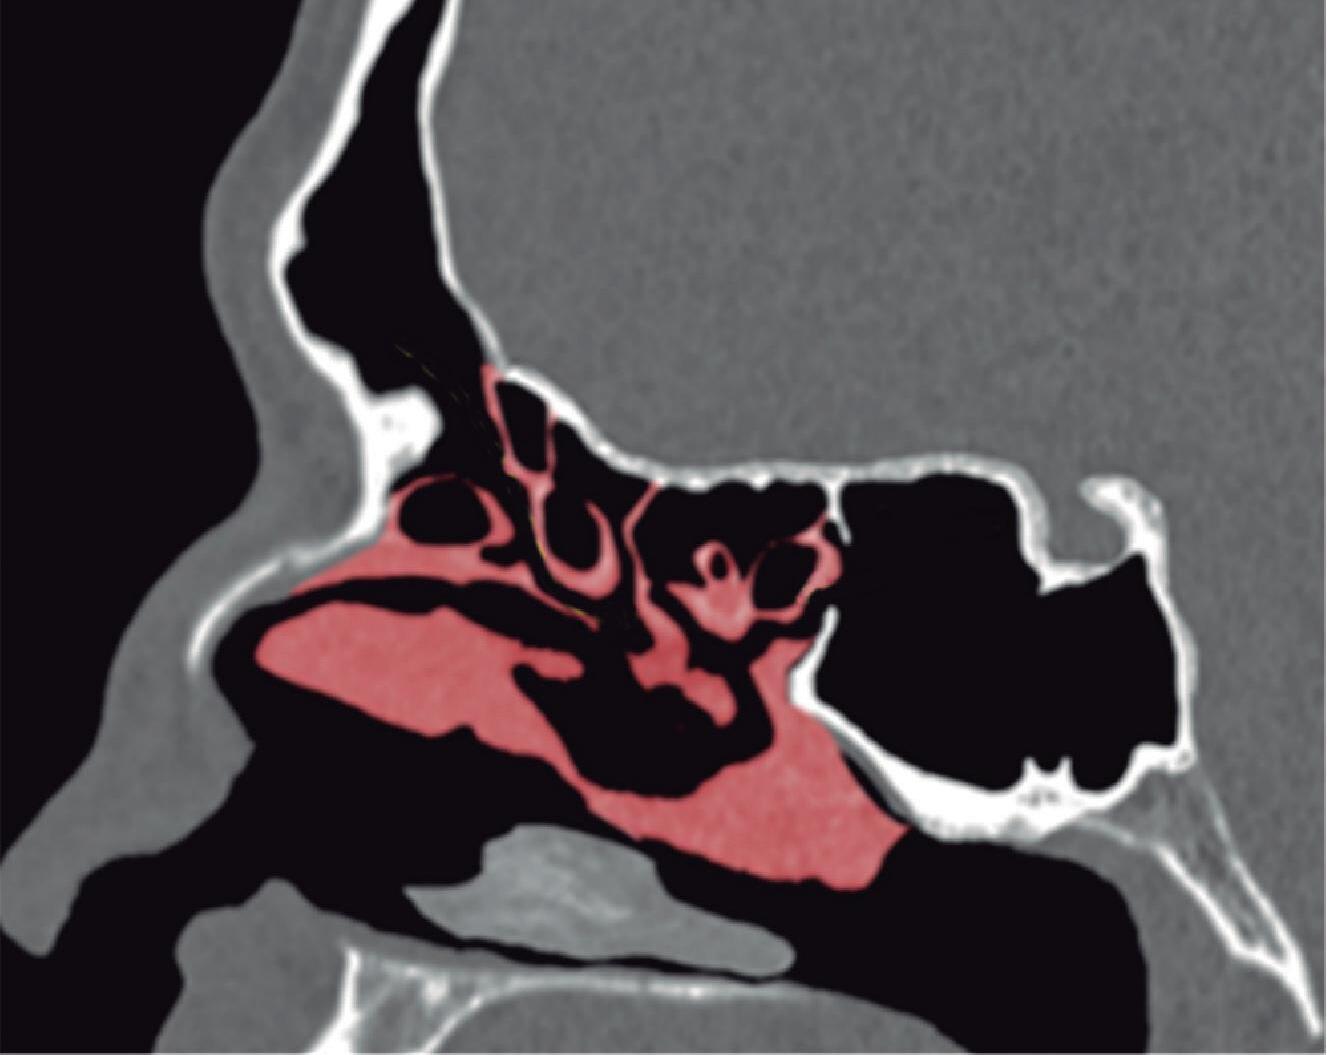

1-4. TC e reconstrução 3D com destaque para estrutura etmoidal (em vermelho), funcionando como câmaras de baixa pressão para drenagem do seio maxilar.

1-7. TC com reconstrução 3D mostrando em vermelho apenas o seio etmoidal e não o osso etmoidal, e sua relação com a fossa nasal, o seio maxilar, órbita e fossa anterior.

1-8. Osso etmoidal e seio etmoidal (amarelo) observar o aspecto incompleto do teto do seio etmoidal que será coberto pelo osso frontal (rosa).

Com pouco parênquima funcional, a concha média é o limite medial do seio etmoidal. Atua aerodinamicamente para impedir que o fluxo inspiratório (rápido, frio e seco) penetre nas câmaras de baixa pressão, além de fechar medialmente estes espaços para que o fluxo expiratório possa ser retido tempo suficiente e permitir ação funcional adequada para os seios frontal, maxilar e esfenoidal. Sendo assim, o seio etmoidal apresenta limites bem estabelecidos:

Fig. 1-45. Limites do seio etmoidal: (1) Limite anterior: junção da placa do agger nasi com o processo frontal do maxilar; (2) limite posterior: parede anterior do seio esfenoidal; (3) limite lateral: processo frontal do maxilar mais anteriormente, osso lacrimal (unguis) e a parede medial da orbita (lâmina papirácea) posteriormente; (4) limite superior: piso da fossa anterior, composto anteriormente pela parte medial do processo orbital do osso frontal e posteriormente pelo plano esfenoidal; (5) limite medial: estrutura vertical da concha média; (6) limite inferior: o seio etmoidal comunica-se livremente com a fossa nasal.